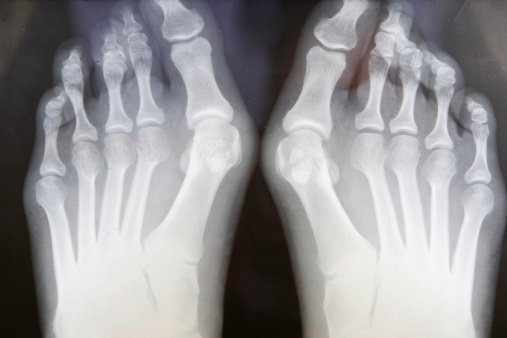

Un juanete se forma cuando el dedo gordo del pie apunta hacia el segundo dedo. Esto causa la aparición de una protuberancia en el borde externo del dedo. ¿Cómo se tratan y previenen? Eso y más aquí ow.ly/V5hd50wBAz5